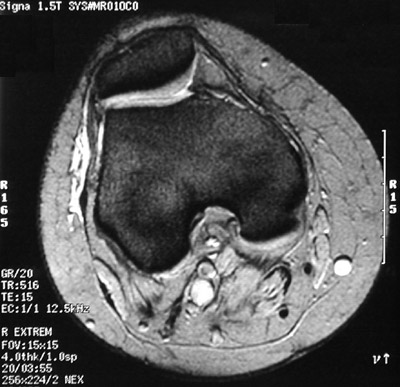

This is a normal axial MRI scan demonstrating the Patella and Articular cartilage of patella and Synovial space and Femur with Medial femoral condyle and Lateral femoral condyle and Articular cartilage of femur and Patellar groove of femur and Intercondylar fossa and Subcutaneum and Sartorius and Gracilis tendon and Great saphenous vein and Deep fascia and Semitendinosus tendon and Semimembranosus and Popliteal artery & vein and Tibial nerve and Common peroneal nerve and Gastrocnemius, medial head and Gastrocnemius, lateral head and Plantaris and Biceps femoris and Iliotibial tract.